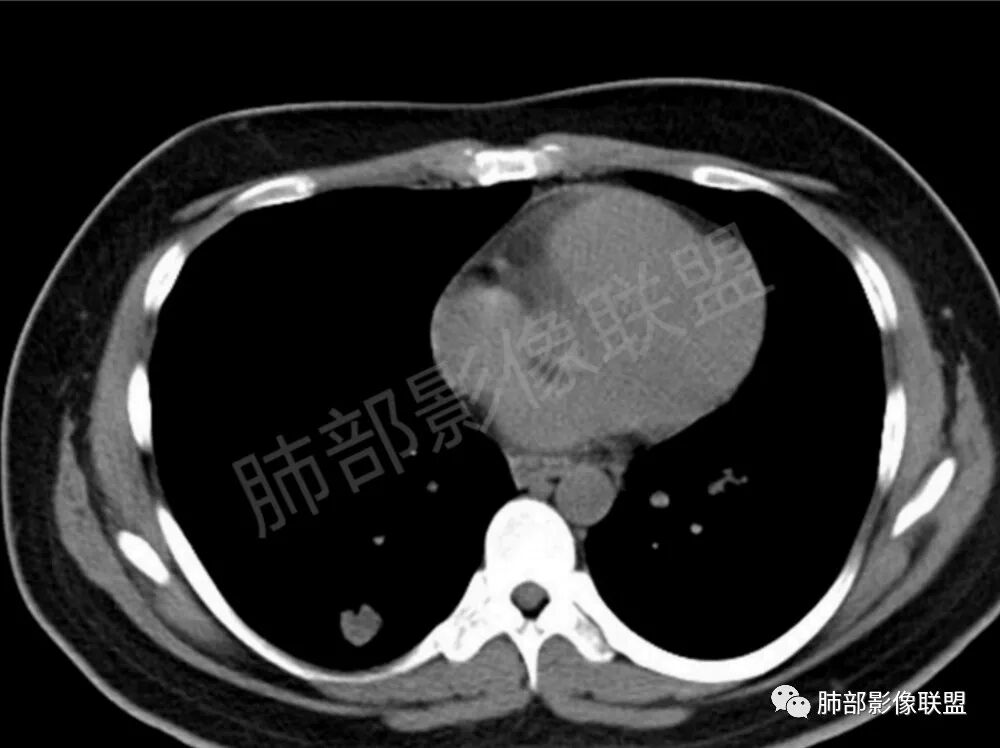

双肺多发结节影,膨隆,边缘光滑,圆顿,沿支气管血管束分布为主,部分贴胸膜,部分见空洞,空气支气管征

两肺多发结节性,大部分位于胸膜下,部分结节周围可见晕征。局部结节内可见扩张的支气管,纵隔淋巴结大,脾大,22岁男,HIV阳性,常规先考虑隐球菌。鉴别淋巴瘤,结核,马儿。

男,22,半年前咳嗽伴少痰,查HIV阳性,痰查TB阳性,既往有肺部斑片影伴空洞、纵隔淋巴结肿大、脾大。SCC、CA50、CA199、FER增高,此次胸部CT:两肺多发结节影,部分沿血管束分布,部分贴胸膜下,大小不一,密度不一,部分较散、边缘模糊,部分较实、圆钝、周围模糊晕,部分结节有支气管进入穿行自然,部分结节有血管分支自如通过。考虑HI∨相关淋巴增殖类病变,淋巴瘤?LYG?鉴别PC、TB。

1、HIV相关淋巴瘤,有HIV阳性,有纵隔及腋窝淋巴结肿大,肺内病灶沿支气管分布(中轴淋巴间质)及胸膜下分布(周围淋巴间质),有脾大,这个是必须要考虑的。但是原来的影像是肺斑片影伴空洞,又有疑问,需要穿刺明确。

影像学缺乏特征性,以支气管血管周围、胸膜下及双肺下叶周边多发结节影最多见,结节易坏死形成空洞,伴有游走性和多变性的特征,结节周围可有磨玻璃样晕征,有时也可见单发结节影、薄壁的囊状阴影或弥漫性浸润影。肺门、纵隔淋巴结肿大少见, 可见胸腔积液和气胸。

类肺炎型∶表现为两肺大片状密度增高影,多位于两肺下野,边缘模糊,病灶内可见支气管气相;